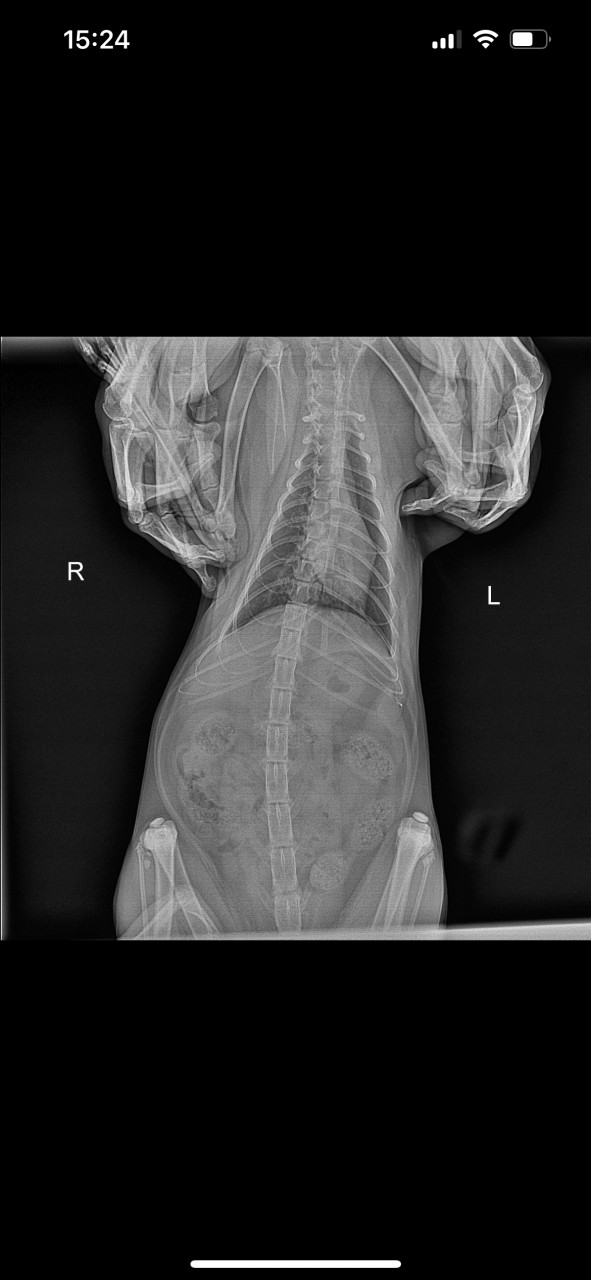

Посмотрите пожалуйста рентген все ли в порядке

Здравствуйте. По представленным рентгеновским снимкам грудной клетки кота визуализируются уплотнённые бронхи и выраженный бронхолёгочный рисунок, что может свидетельствовать о хроническом бронхите, астмоидном синдроме или воспалении дыхательных путей. Сердце и диафрагма выглядят без грубых отклонений, но для точной оценки необходимо заключение ветеринарного рентгенолога. Хрипы у кота  это не норма, особенно при хроническом течении. Обратитесь к ветеринару для назначения терапии.